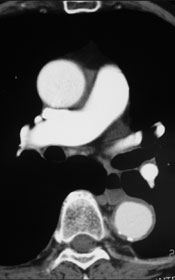

胸部CAT Scan所見

CAT scanにて弓部瘤の診断。

血管造影にて適応があればGore社TAG stent留置術

平成18年7月CC出現。

平成18年8月当院紹介受診。

【既往歴】

CHF、高血圧(+) 喫煙歴(20本×30年)

【治療計画】